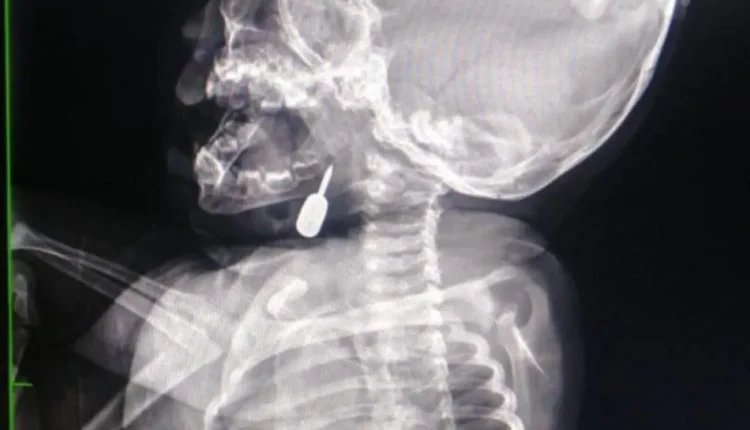

وفي تدخل طبي عاجل، أنقذ الدكتور السبول حياة طفل يبلغ من العمر أحد عشر شهراً، بعد أن وصل إلى قسم الطوارئ وهو يعاني من حالة اختناق حادة نتيجة وجود جسم معدني عالق في منطقة الحنجرة. وقد تم استخراج الجسم بنجاح، مما أسهم في إنقاذ حياة الطفل.